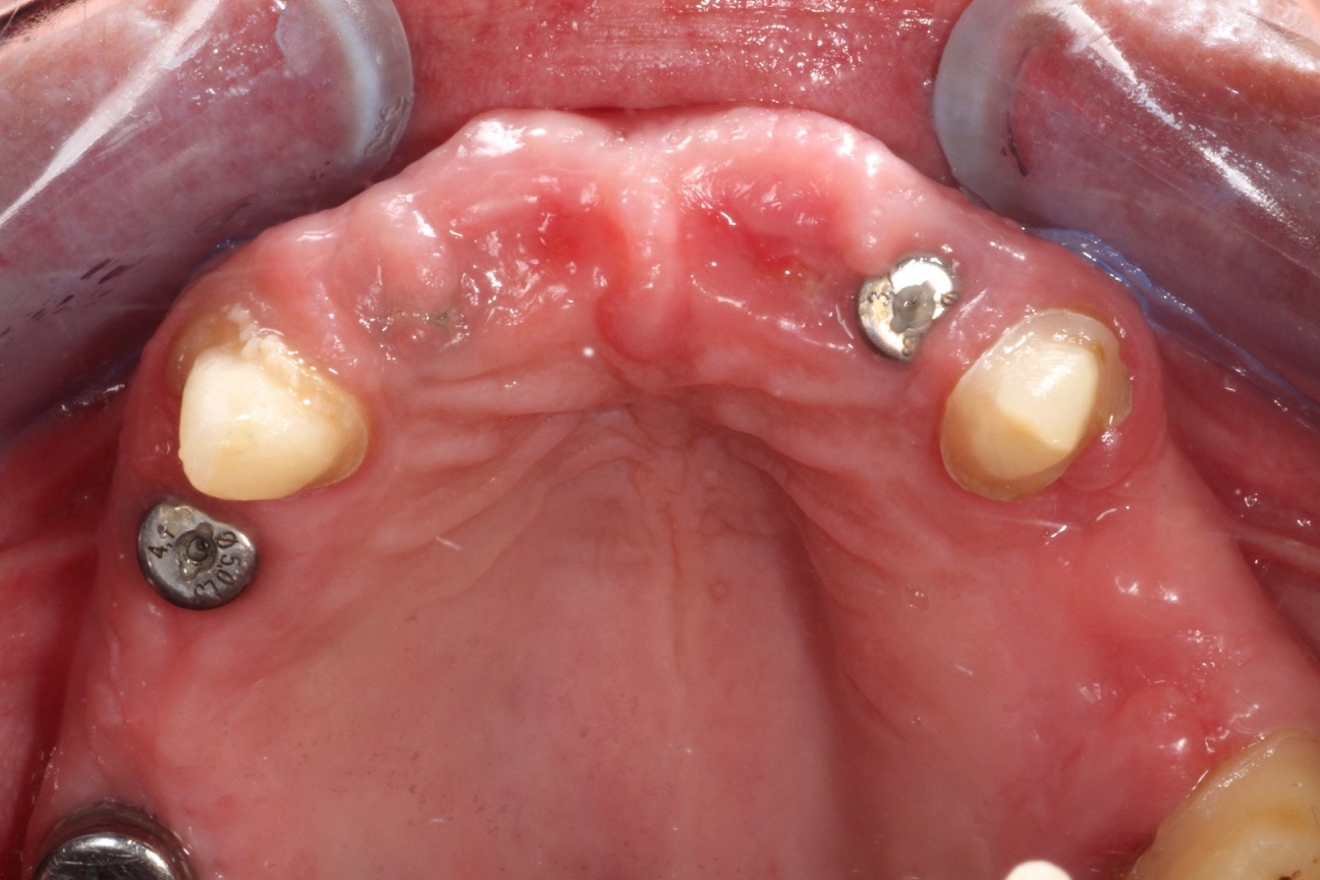

The 58-year-old, non-smoking and systemically healthy female patient was referred by her dentist to our dental clinic for implant treatment. The patient’s main complaints were poor aesthetics in the upper jaw, including a high smile line and distinct tooth pattern anomalies in the anterior maxilla (Figs. 1 & 2), as well as masticatory discomfort. Teeth #17, 15 and 27 were missing and had not undergone any prosthetic treatment, whereas the five missing teeth in the premolar and molar areas on both sides of the mandible had been replaced with a removable partial denture. All remaining teeth were affected by Stage IV periodontitis according to the 2017 Classification of Periodontal and Peri‐implant Diseases and Conditions, displaying a mean periodontal pocket depth of 5.6 mm.7 Mean bleeding on probing and mean plaque index were 70% and 80%, respectively. With respect to periodontal parameters, as well as to oral hygiene measures (visible calculus and dental plaque), the patient’s oral hygiene was graded as poor. The patient had been treated elsewhere with two implants in the posterior maxilla in order to replace the right first premolar and first molar (Fig. 3). She had a thick flat biotype, according to a definition introduced in 1977.8, 9

After obtaining informed consent from the patient, we would start dental rehabilitation in the maxilla, and we opted for a two-stage surgical approach after initial therapy. Initial therapy would consist of systematic periodontal treatment and regular recalls with instructions and checks for dental hygiene over a period of three months. The first stage of rehabilitation of the maxilla would consist of partial extraction therapy in conjunction with Type 1 implant placement in the regions of the teeth #12 and 22 according to the Proceedings of the Fourth ITI Consensus Conference and ridge preservation in the region of teeth #24 and 25 with particulate dentine, obtained and processed from the two extracted left maxillary premolar teeth.10 Owing to increased tooth mobility and the obvious poor buccal bone volume, as displayed on the CBCT scan (CRANEX 3D Ceph, Soredex, KaVo Kerr), regions #11 and 21 were not suitable for the socket shield technique in conjunction with implant placement (Fig. 4). Both central incisors were to be treated with the submerged root technique instead, in order to prevent damage of the buccal socket wall and volume loss of the alveolar ridge after tooth extraction. With both roots in place, a physiological pontic site development for the definitive restoration would be enabled. Based on periodontal re-evaluation after the initial therapy, only the two maxillary canines were considered worth preserving. The left first molar was to be temporarily retained in order to serve, in conjunction with the two canines, as an additional abutment tooth for fixation of the temporary bridge during the healing period. Crown preparation of the three remaining teeth would be done before surgical treatment, in order to prefabricate a temporary bridge for immediate fixed provisionalisation after the first surgery. The second surgical stage would consist ofimplant placement in region #24, performing of the socket shield technique on the mesiobuccal root, submersion of the distobuccal root and extraction of the palatal root of tooth #26 before immediate implant placement. Definitive prosthetic treatment would be performed after a transgingival implant healing period of at least three months, applying a conventional implant loading protocol with fixed bridges.11